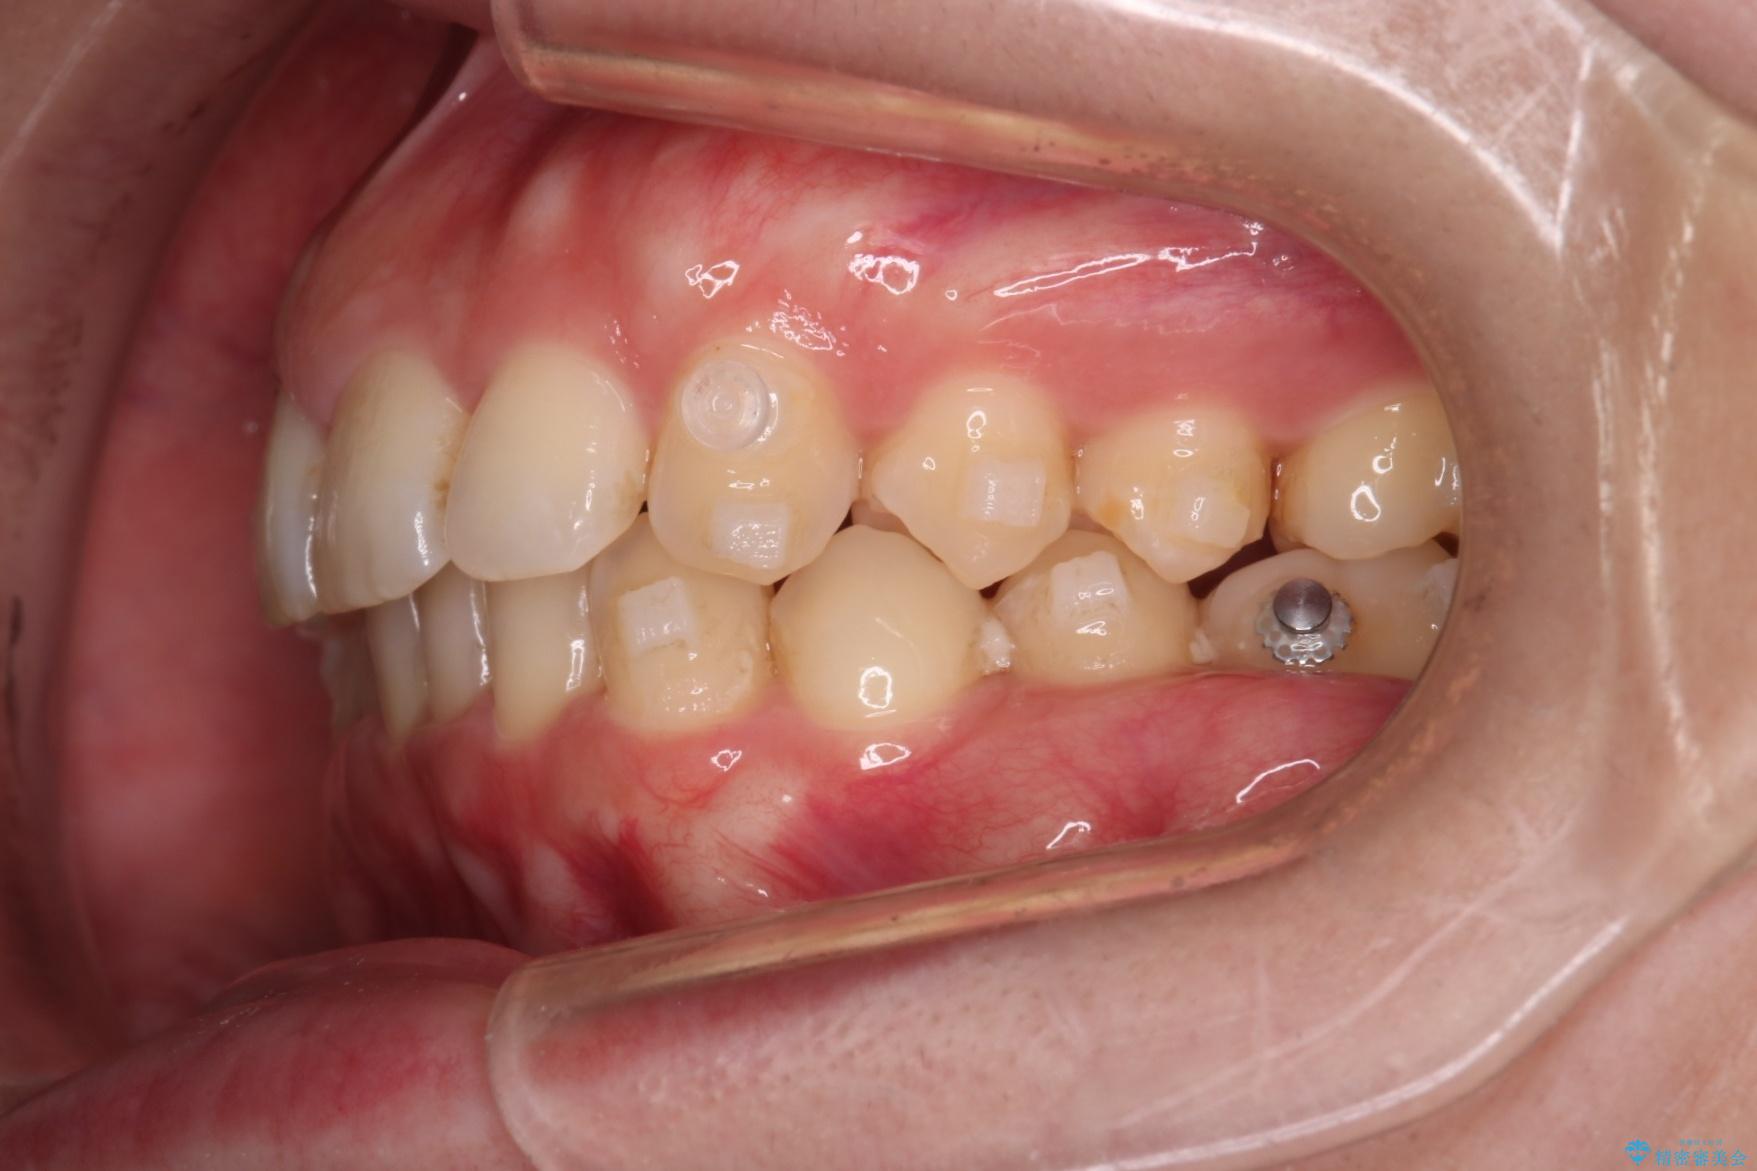

右側臼歯部の咬合改善のために、臼歯部のみ部分的なワイヤー矯正を行い、咬合改善がみられてからインビザラインにて全体的な矯正を行なっていく治療計画を立てました。

噛み合わせをよくするために、ワイヤー矯正とインビザライン矯正のどちらの期間も必要な箇所にゴム掛けを行いながら治療を行いました。